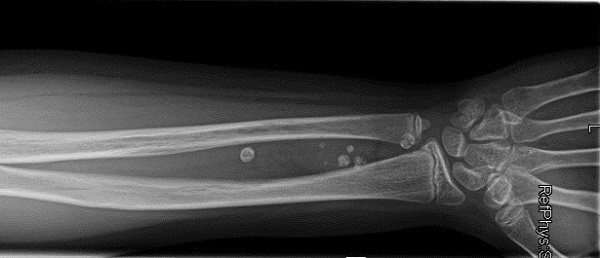

Ante la sospecha de malformación vascular se amplía el estudio mediante ecografía que sugiere una malformación de bajo flujo y se completa con una resonancia magnética (Fig. 2) que confirma el diagnóstico de malformación de tipo venoso en compartimento flexor del antebrazo derecho que asocia zonas de trombosis.

Figura 2. Resonancia magnética

En cuanto a técnicas de imagen, la radiografía detecta la presencia de flebolitos orientando el diagnóstico desde Atención Primaria. La lesión vascular de flujo lento se confirmará mediante ecografía Doppler. Es fundamental remitir a cirugía vascular para completar estudio mediante resonancia magnética que ayude a definir la extensión y decidir el abordaje adecuado.